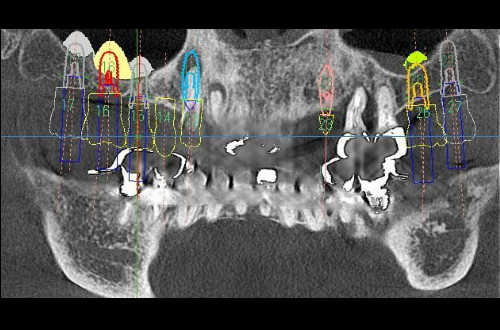

晴れた日には医院旗を揚げることもあります。 スタッフ一同です、よろしくお願いいたします。 市内では早く、2012.05に歯科用CT撮影装置を導入致し、すでに10年以上の経過しました。インプラント治療その他に計り知れない有効性を感じております。 2017.06.には大きな範囲の撮影が出来るLタイプにバージョンアップしました。他院からの撮影依頼もお受け致します。 人間工学に基づいた設計の寝心地も良い、歯科診療ユニット Lタイプにて撮影しました。 CTは骨幅などインプラント治療計画などに活用して無くてはならないものになっております。 インプラントの埋入シミュレーション画像です。 埋入位置でのCT断層画像です。 必要に応じてCTデータから、あごの原寸大模型を作製します。 歯を長く残すために必要な根管治療も、少ない回数で真剣に取り組んでおります。 動く踊る落ちる入れ歯を、アタッチメントで安定させてみませんか? この1本のインプラントとアタッチメントは、合わない入れ歯を噛める入れ歯に変身させる可能性を持っています。 インプラントの埋入計画や頭蓋骨のCT画像です。画像入りの分析計画書とお見積もり同意書を作成しています。 インプラント治療は、1本欠損から14本欠損まで回復することが可能です。 診療室全景です。明るく清潔さを心がけております。 大町歯科加藤医院をスナップでご紹介します。 2007年春にリニューアルしました。 受付・待合室です。ウォーターサーバーやPC、Wi-Fi、スマートフォン充電器なども備えています。 Plastic Lounge(多目的室)主に第2待合室として使用しております。 院長の好みの書籍も多数並べてあります。 玄関を入って、すぐ左側にあります。付き添いの方もテレビなど見てリラックスできます。 元苫小牧大町の在住だった画家の山田 啓貴氏の作品です。(クリック!.) 第2待合室から第1待合室への階段を望む。 駐車場は10台ほど駐車できます。 大町歯科の夕景です。 階段踊り場の花は毎週替えています。 1928年に追分町から移転開業以来、95年目を迎えました。 インプラント治療は1000本以上の埋入実績があり、低侵襲な治療を心がけております。お気軽にご相談ください。 御来院をお待ちしております。